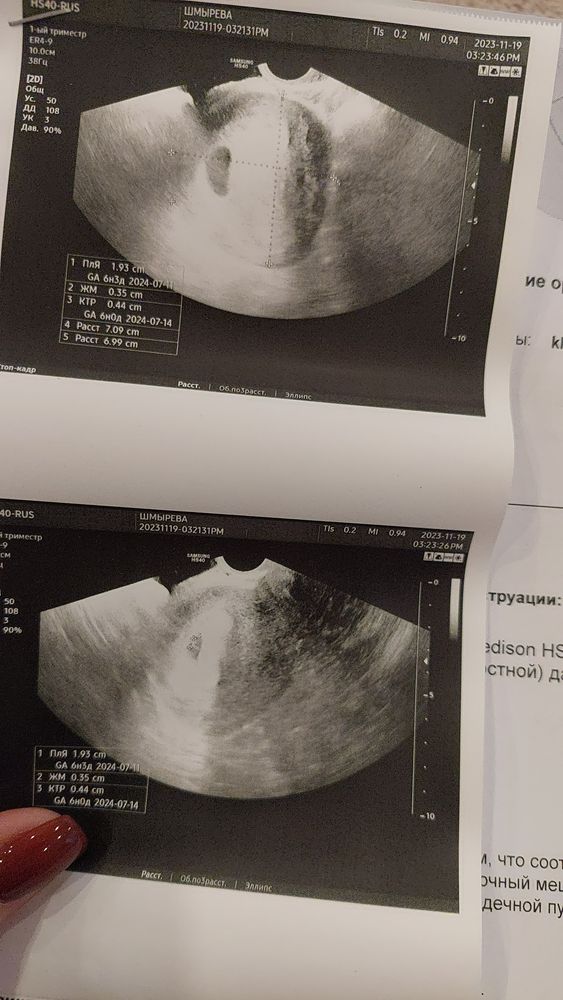

УЗИ на 7 акушерской неделе

Скажите пожалуйста завтра 7 ровно акушерство недель ,все ли в порядке у нас по показателям ?на фото вверху ПЯ на втором плодное яйца и эмбрион )

Все норм,только срок меньше,по ктр 6 недель у вас,видимо овуляция поздняя была